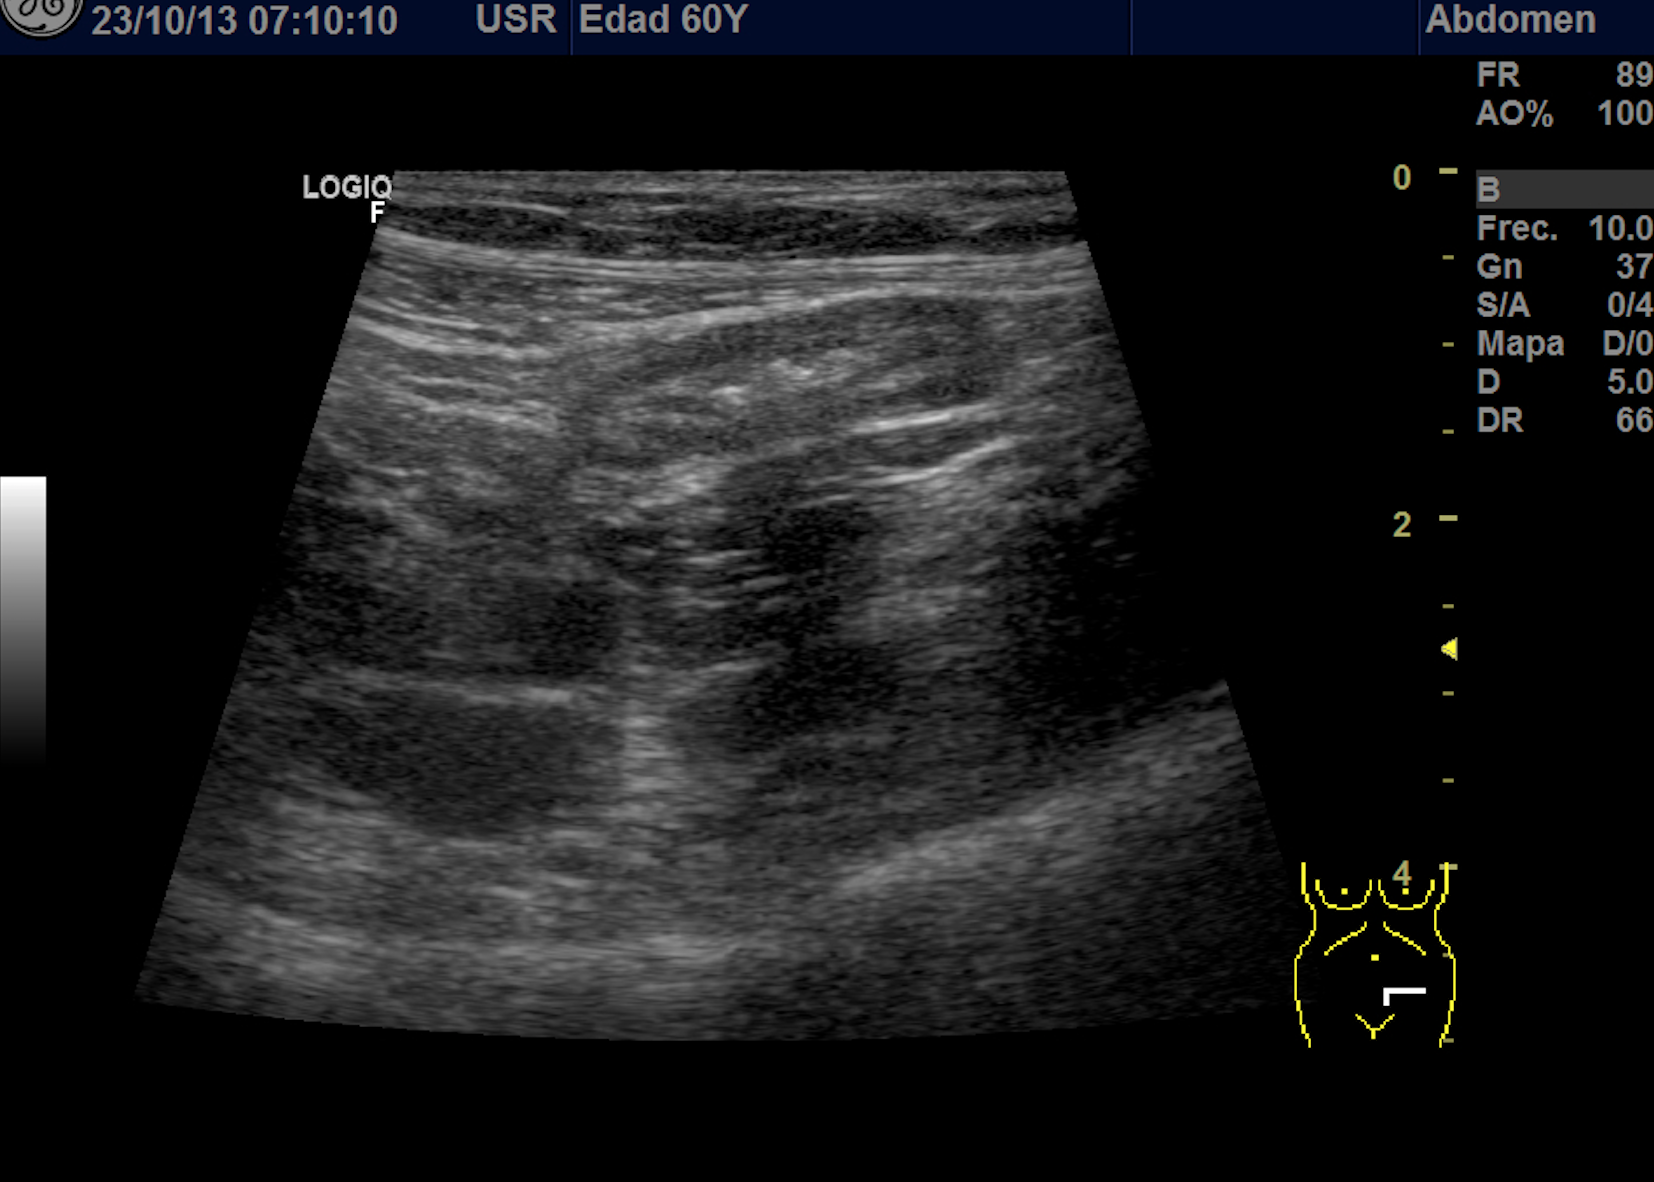

Se explora FII-hipogastrio y en el punto de más dolor se observa engrosamiento de asas de intestino grueso sin peristaltismo y con signos de edema de la grasa adyacente. No líquido libre.

También se realiza ecografia en urgencias del hospital.

En el hospital se realiza una nueva ecografía en el servicio de radiología confirmando el diagnóstico de sospecha: diverticulitis aguda en sigma distal sin datos de complicación. Hinchey 1A.